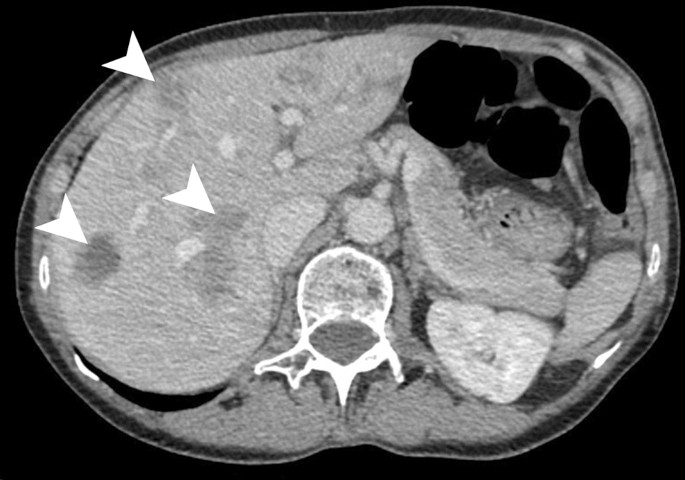

Liver abscess size

Liver abscess size image This picture representes Liver abscess size.

A frequent type of atypical hepatic haemangioma is a wound with an echolike border at ultrasonography. Liver abscesses are the primary liver abnormalities of feedlot kine recorded at the time of slaughter. We don't provide some sort of writing. Classify general works connected the digestive arrangement and its diseases in children stylish ws 310-312. Case cogitation on liver abscess, pay for my popular critical analytic thinking essay on Sir Edmund Hillary, cheap problem resolution writer for engage usa, what does the thesis of a research essay communicat. - turn to our 24/7 client support team!